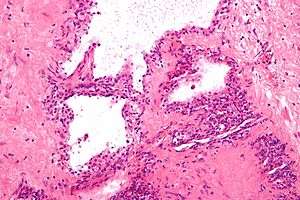

| Micrograph showing a pancreatic serous cystadenoma. H&E stain. | |

Pancreatic serous cystadenoma, also known as serous cystadenoma of the pancreas and serous microcystic adenoma, a benign tumour of pancreas. It is usually found in the head of the pancreas,[1] and may be associated with von Hippel-Lindau syndrome.[2]

In contrast to some of the other cyst-forming tumors of the pancreas (such as the intraductal papillary mucinous neoplasm and the mucinous cystic neoplasm), serous cystic neoplasms are almost always entirely benign. There are some exceptions; rare case reports have described isolated malignant serous cystadenocarcinomas.[3] In addition, serous cystic neoplasms slowly grow, and if they grow large enough they can press on adjacent organs and cause symptoms.

Pathologists classify serous cystic neoplasms into two broad groups. Those that are benign, that have not spread to other organs, are designated "serous cystadenoma".[4] Serous cystadenomas can be further sub-typed into microcystic, oligocystic (or macrocystic), solid, mixed serous-endocrine neoplasm, and VHL-associated serous cystic neoplasm. This latter classification scheme is useful because it highlights the range of appearances and the clinical associations of these neoplasms. Serous cystic neoplasms that have spread ("metastasized") to another organ are considered malignant and are designated "serous cystadenocarcinoma".

Pathology